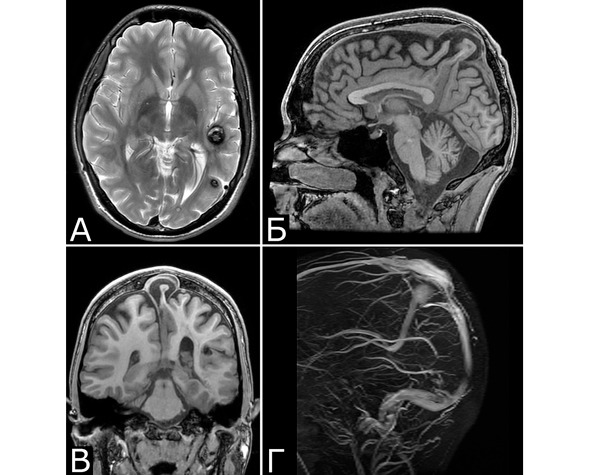

У 6 больных каверномы сочетались с венозными ангиомами и аномалиями венозной системы. Крупные патологические вены, расположенные в непосредственной близости к КМ, часто обнаруживают при МРТ или на операции, в связи с чем многие авторы рассматривают их как единую патологию (28, 93, 154, 351, 357). Тем не менее, в ряде случаев кавернозные и венозные мальформации можно четко дифференцировать как самостоятельные образования, особенно если они находятся в разных отделах мозга. У двух больных патология венозной системы представляла собой аномалию сразу нескольких крупных венозных коллекторов головного мозга (рис. 2).

Рис. 2. Б-ной П, 22 г. Сочетанная сосудистая патология мозга: Множественные КМ головного мозга. Аномалия развития венозной системы мозга. А – КМ височной, теменной и затылочной долей слева (МРТ, режим Т2, аксиальная проекция). Б, В – аномалия развития костей и оболочек мозга в виде локальной деформации внутренней костной пластинки и губчатого вещества теменных костей в области впадения патологической вены в ВСС. Расщепление аномального ВСС на две лакуны, пролабирование мозга в область дефекта (МРТ, режим Т1, сагиттальная и фронтальная проекции). Г – аномалия венозной системы в виде отсутствия прямого синуса, формирования крупной патологической вены, впадающей в заднюю треть ВСС (МРТ-АГ, сагиттальная проекция)